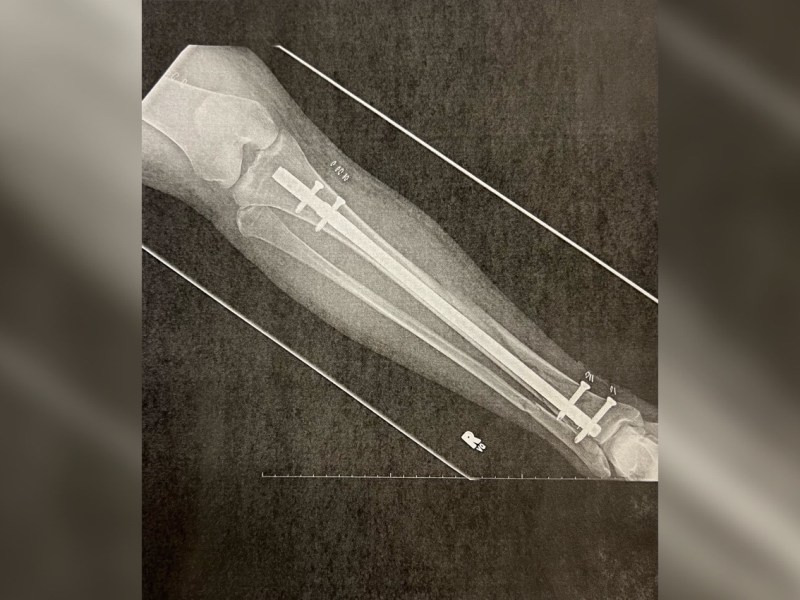

Being broke, broken and brazen

A quick update – I am still unemployed and currently with one working leg. But as Sia said, I am titanium!